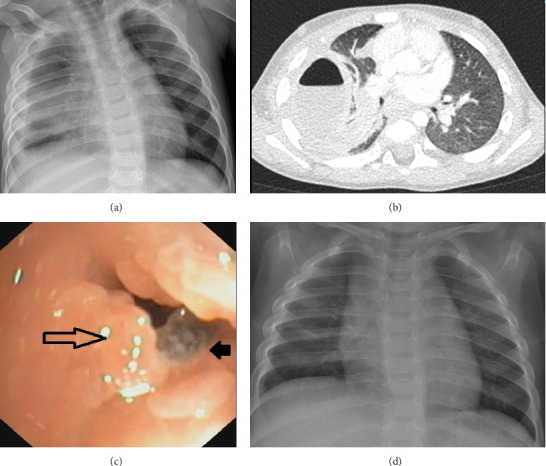

Eikenella corrodens is a commensal bacterium of the buccal cavity and rarely causes lower respiratory infections in healthy children. Two young patients with persistent pleuropneumonia caused by E. corrodens are presented. In both cases, an obstructing endobronchial foreign body was found. Removal of the foreign bodies allowed complete recovery. A local and literature review demonstrated E. corrodens causing empyema in only four other cases, all with comorbidities. We conclude that in cases of persistent pneumonia in healthy children due to Eikenella corrodens, an aspirated foreign body should be suspected.